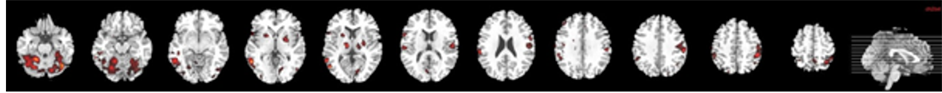

The processing of neutral faces compared with baseline (21 foci) activated significantly: frontal areas (right medial frontal gyrus, right frontal inferior, bilateral precentral gyrus), temporal areas (right middle temporal and right temporal superior), parietal regions (right supramarginal gyrus, left superior parietal lobule, left postcentral gyrus), bilateral cerebellum, and subcortical area (left putamen and right globus pallidus) cerebellum (cluster p < 0.001, false discovery rate [FDR] p < 0.001; Table 3, Figure 3(a)).

2.4.2. Processing 100% Fearful Faces

The processing of fearful faces compared with baseline (24 foci) was associated with significant increase of BOLD signal in: the visual regions (left inferior occipital gyrus and left fusiform gyrus), temporal areas (right middle temporal and inferior gyri), parietal regions (left parietal superior, bilateral postcentral gyri, bilateral angular gyrus), and the bilateral cerebellum (cluster p < 0.001, false discovery rate [FDR] p < 0.001; Table 3, Figure 3(b)).

Figure 3. Brain maps of neural activation in response to both neutral (a) and 100% fearful facial expressions (b) compared with fixation cross in the healthy control group.

Before therapy of B.D. recruitment was larger in the left hemisphere, both with neutral and fearful faces. In response to neutral faces visual cortex was significantly activated, including calcarine and fusiform gyrus. Before treatment was provided, perception of 100% fearful expressions recruited cerebellum, precentral gyrus and visual regions but not amygdala. We found that processing of fearful faces in healthy controls was associated with increased activation in visual brain regions including fusiform gyrus, temporal and parietal areas and bilateral cerebellum; which again corresponded with robust neuroimaging data.